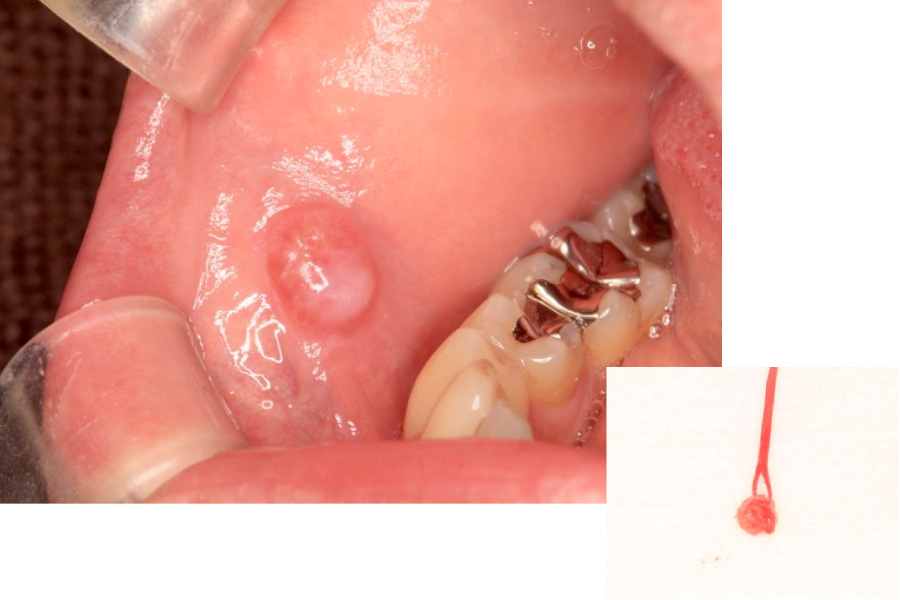

粘液嚢胞(口内炎・水ぶくれ)

外科的処置で治療した症例

- 頬の内側を噛んでしまったあと、水ぶくれができては潰れ、再び膨らむという状態を繰り返しているとのことで来院。

違和感と不快感を改善したいとのご希望がありました。

- 頬粘膜に発生した粘液貯留嚢胞を外科的に切除しました。

局所麻酔下で嚢胞とその原因となっている唾液腺組織を丁寧に除去し、再発を防ぐために粘膜下をきれいに処理しました。

手術後は軽度の腫れがみられましたが、経過良好で再発はありませんでした。